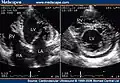

Two-dimensional apical four chamber and parasternal short axis images at the level of the ventricles show dilatation of both ventricles, multiple trabeculae and intertrabecular recesses in inferior, lateral, anterior walls, middle and apical portions of the septum and apex of the left ventricle. [1] -

Transthoracic two-dimensional echocardiogram in apical four chamber and parasternal short axis at the level of both ventricles demonstrate dilatation, deep trabeculae and intertrabecular recesses in the inferior, lateral, anterior walls, middle and apical portions of the septum and apex of the left ventricle. [3] -